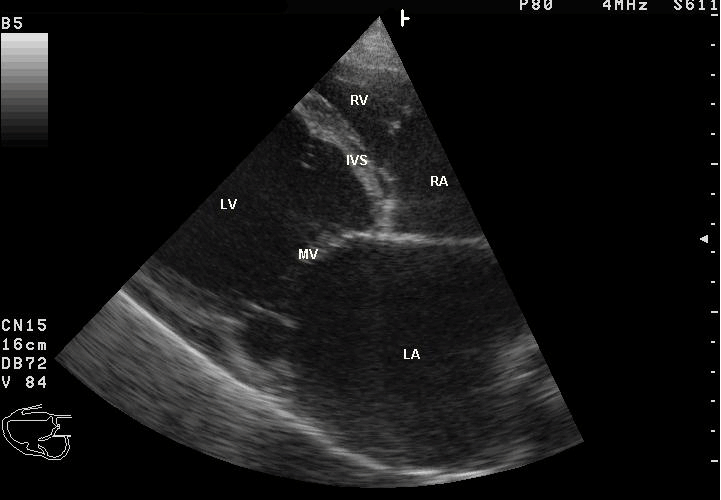

13時からエコーの講義。続いて、実習室に移って実習。

• 14:50〜 エコーのデモ。3班ずつにわかれて参加。各組男子1名が被験者のボランティア。最後に、希望者と最終組のボランティアが再度参加。15:50終了

アイキャッチ画像:Wikimedia